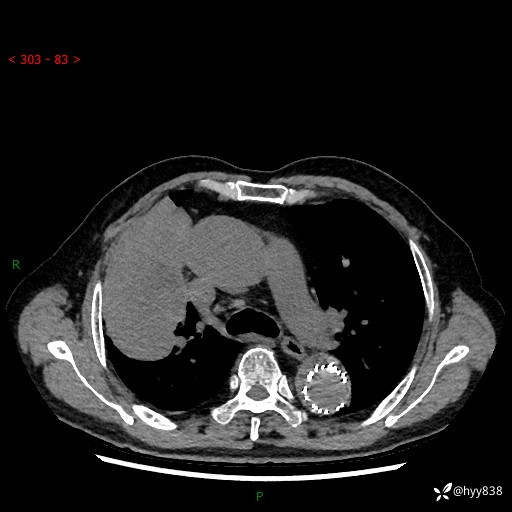

辅助检查:CT

增强动脉期